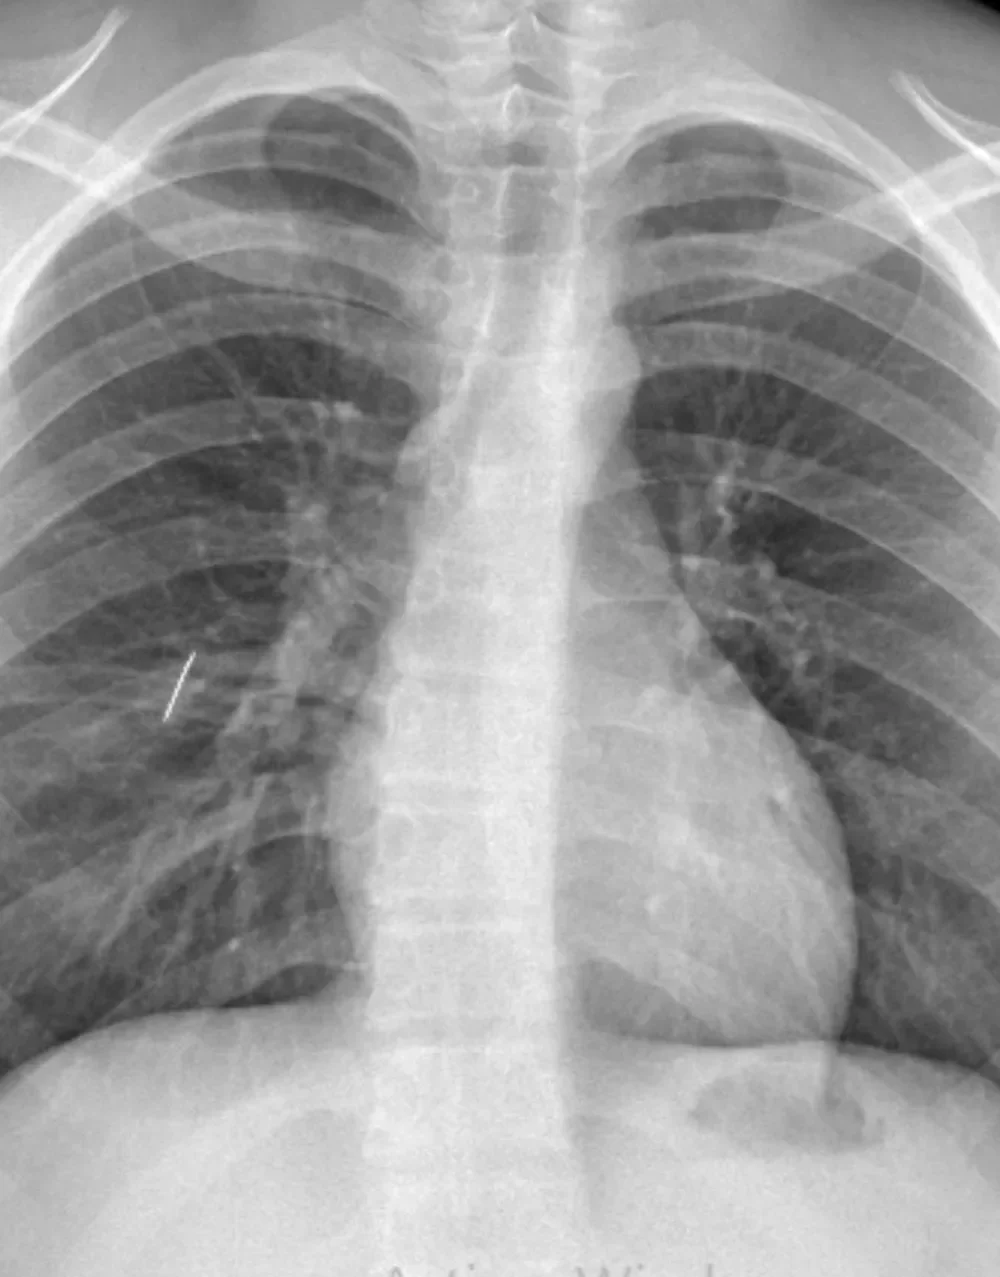

En una cirugía de alta complejidad extrajeron un objeto metálico del pulmón de un joven del interior